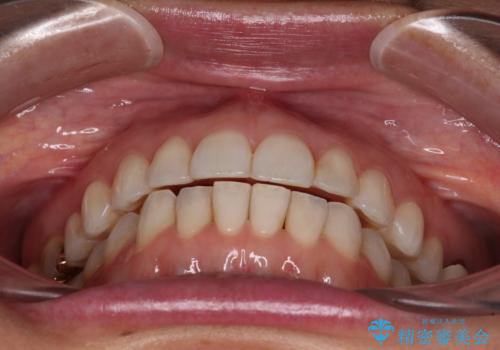

ちょっとしたデコボコをしっかりと改善したい インビザライン矯正

- 前歯のデコボコと上下スペースと前歯の隙間を気にして来院された患者様です。

目立たない装置を希望とのことでインビザラインにより、デコボコを解消しつつ、上下の前歯の隙間を閉じていくこととしました。

デコボコはあっという間に解消されましたが、上下前歯の隙間がなかなか解消されませんでした。

飲み込みの際に舌を前方に突出する癖があり、飲み込みの度に前歯に強く接触していたため、上下前歯の隙間が維持されていました。

舌の訓練を徹底していただいたことで、徐々に隙間は解消され、きれいな歯列に整えることができました。